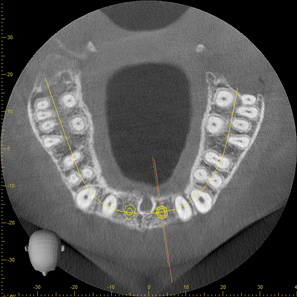

Fig 2. CBCT images: axial (Fig 2) and cross-sectional (Fig 3) views, and 3D reconstruction view (Fig 4) with virtually planned implant Nos. 8 and 9.

Figure 2

Fig 3. CBCT images: axial (Fig 2) and cross-sectional (Fig 3) views, and 3D reconstruction view (Fig 4) with virtually planned implant Nos. 8 and 9.

Figure 3

Fig 4. CBCT images: axial (Fig 2) and cross-sectional (Fig 3) views, and 3D reconstruction view (Fig 4) with virtually planned implant Nos. 8 and 9.

Figure 4

For dental implant-based treatment, the planning phase begins with collection of basic data sets; this is digital touchpoint 1. It includes: (1) a cone-beam CT (CBCT) to view edentulous areas or failing tooth structure, bone, and anatomic landmarks under the soft tissue (Figure 2 through Figure 4); and (2) an intraoral optical scan (IOS) or a scanned model or impression to record the soft tissue and tooth anatomy (Figure 5). The superimposition of the digital imaging and communications in medicine (DICOM) files from the CBCT and the standard tessellation language (STL) files from the IOS allows visualization of how bone, dental structures, and soft tissues relate. Both digital data points are key to implant selection and determining the surrounding bone-grafting needs. An initial treatment plan includes determining the desired implant manufacturer/implant design, size, and positions; these decisions remain the responsibility of the clinician (restoring and surgical team members) and not the technician or planning team.